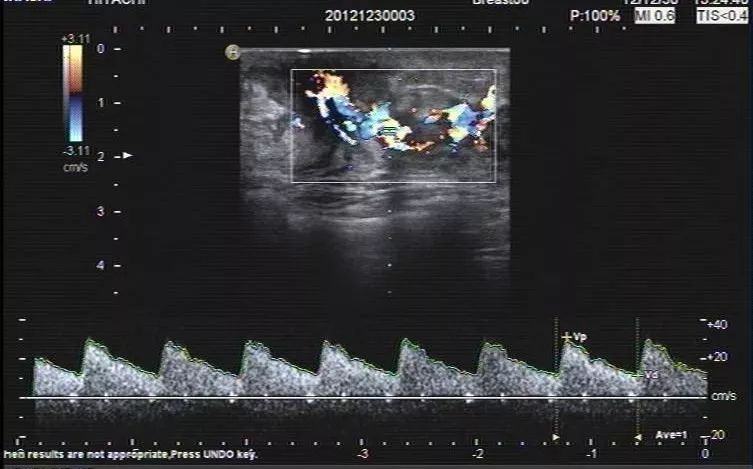

2、彩色多普勒及频谱多普勒表现

急性乳腺炎的彩色多普勒表现无特异性。多数乳腺腺体内的血流信号轻度增加,形成脓肿时脓肿壁上可探及低速低阻的血流,与其他乳腺良性疾病的阻力指数相似,而异于乳腺恶性肿瘤的血管阻力,后者阻力指数一般较高。